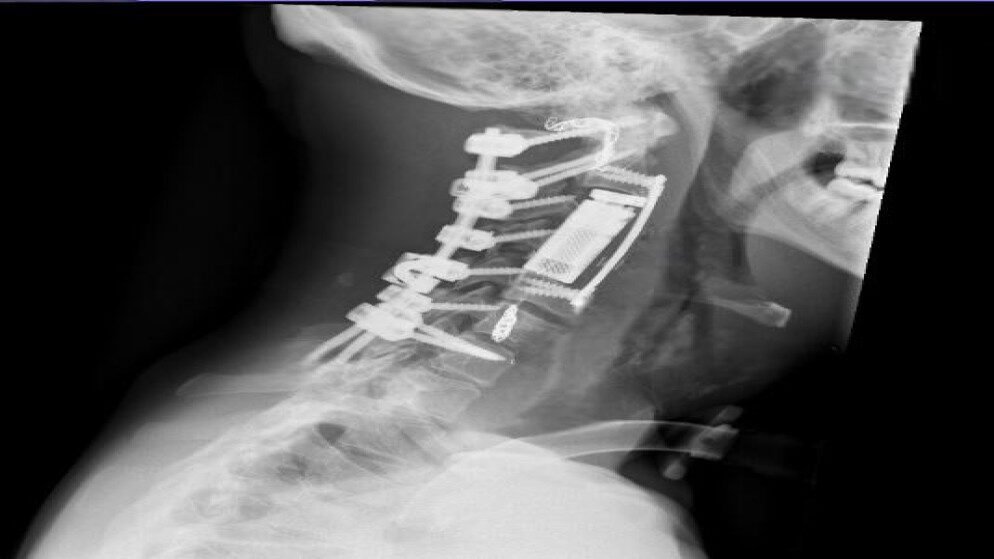

وشملت المرحلة الجراحية تثبيت العمود الفقري من الفقرة العنقية الأولى إلى السابعة، وتحرير النخاع الشوكي، ثم استئصال الورم والفقرات المصابة بالكامل من الجهة الأمامية للعنق بطريقة “الاستئصال الكامل في كتلة واحدة”. تم بعدها تعويض الفقرات المستأصلة بقفص فقري تمددي، وتثبيت أمامي لضمان استقرار العمود الفقري.